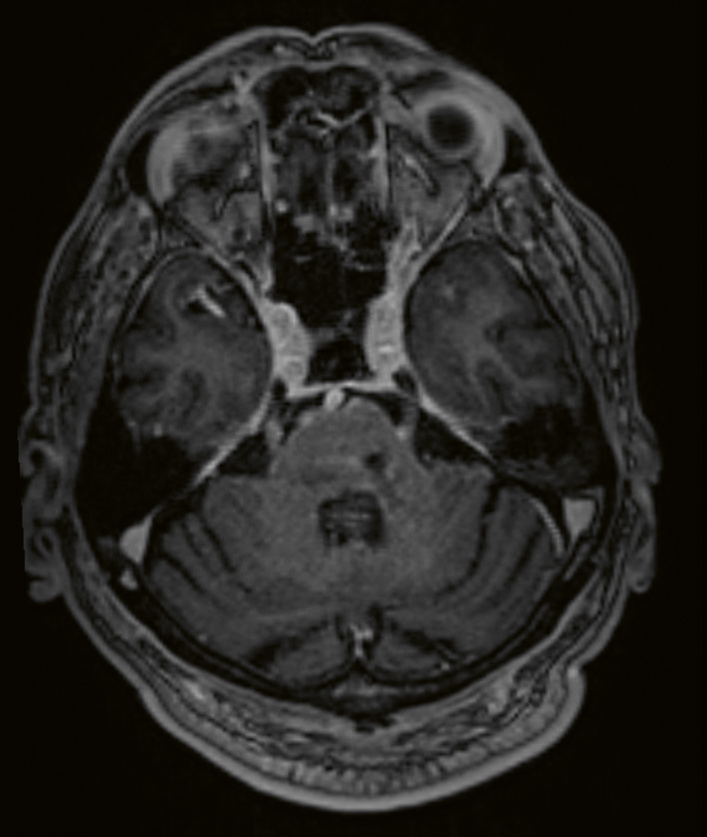

Vid misstanke om neurosarkoidos är det viktigt att utföra en MR-undersökning av hela CNS, det vill säga både hjärnan och ryggmärgen. Dessutom bör MR alltid göras med kontrast. Leptomeningeal uppladdning, både diffus och nodulär i skallbasen, är det vanligaste MR-fyndet (T1-viktad sekvens) vid neurosarkoidos, med en förekomst på 56 procent. Vid spridning till de basala hjärnhinnorna kan man även se påverkan på de lägre kranialnerverna (Figur 1 och 2). Pakymeningit är mindre vanlig som isolerat fynd vid neurosarkoidos (Figur 3) [32, 33]. Kontrastuppladdning i de drabbade kranialnerverna ses ibland vid MR, men inte alltid [34]. MR av hypofysen visar oftast en multi­fokal förstoring och kontrastuppladdning av främre hypofysen och infundibulum, och ibland även av hypo­talamus [35, 36]. Peri­ventrikulära och djupa vitsubstanslesioner, som är högsignalerande på FLAIR- och T2-sekvenser, är vanliga vid neurosarkoidos och kan vara svåra att särskilja från vaskulära förändringar [37]. Hydrocefalus och tumörliknande förändringar förekommer, men är ovanliga fynd vid neurosarkoidos [37]. Vid misstanke om vaskulit bör susceptibilitetsviktad MR-sekvens (SWI), kärlväggs­avbildning och konventionell angiografi utföras. Framträdande medullära vener har beskrivits som ett specifikt fynd vid neurosarkoidos [38].

Figur 3. MR av hjärnan, T1-viktad, Gd+.Bilden visar utbredda kontrastladdande pakymeningeala förtjockningar bilateralt längs tentoriet, i falx mellan lillhjärnshemisfärerna och utmed sinus cavernosus, mer uttalade på höger sida.